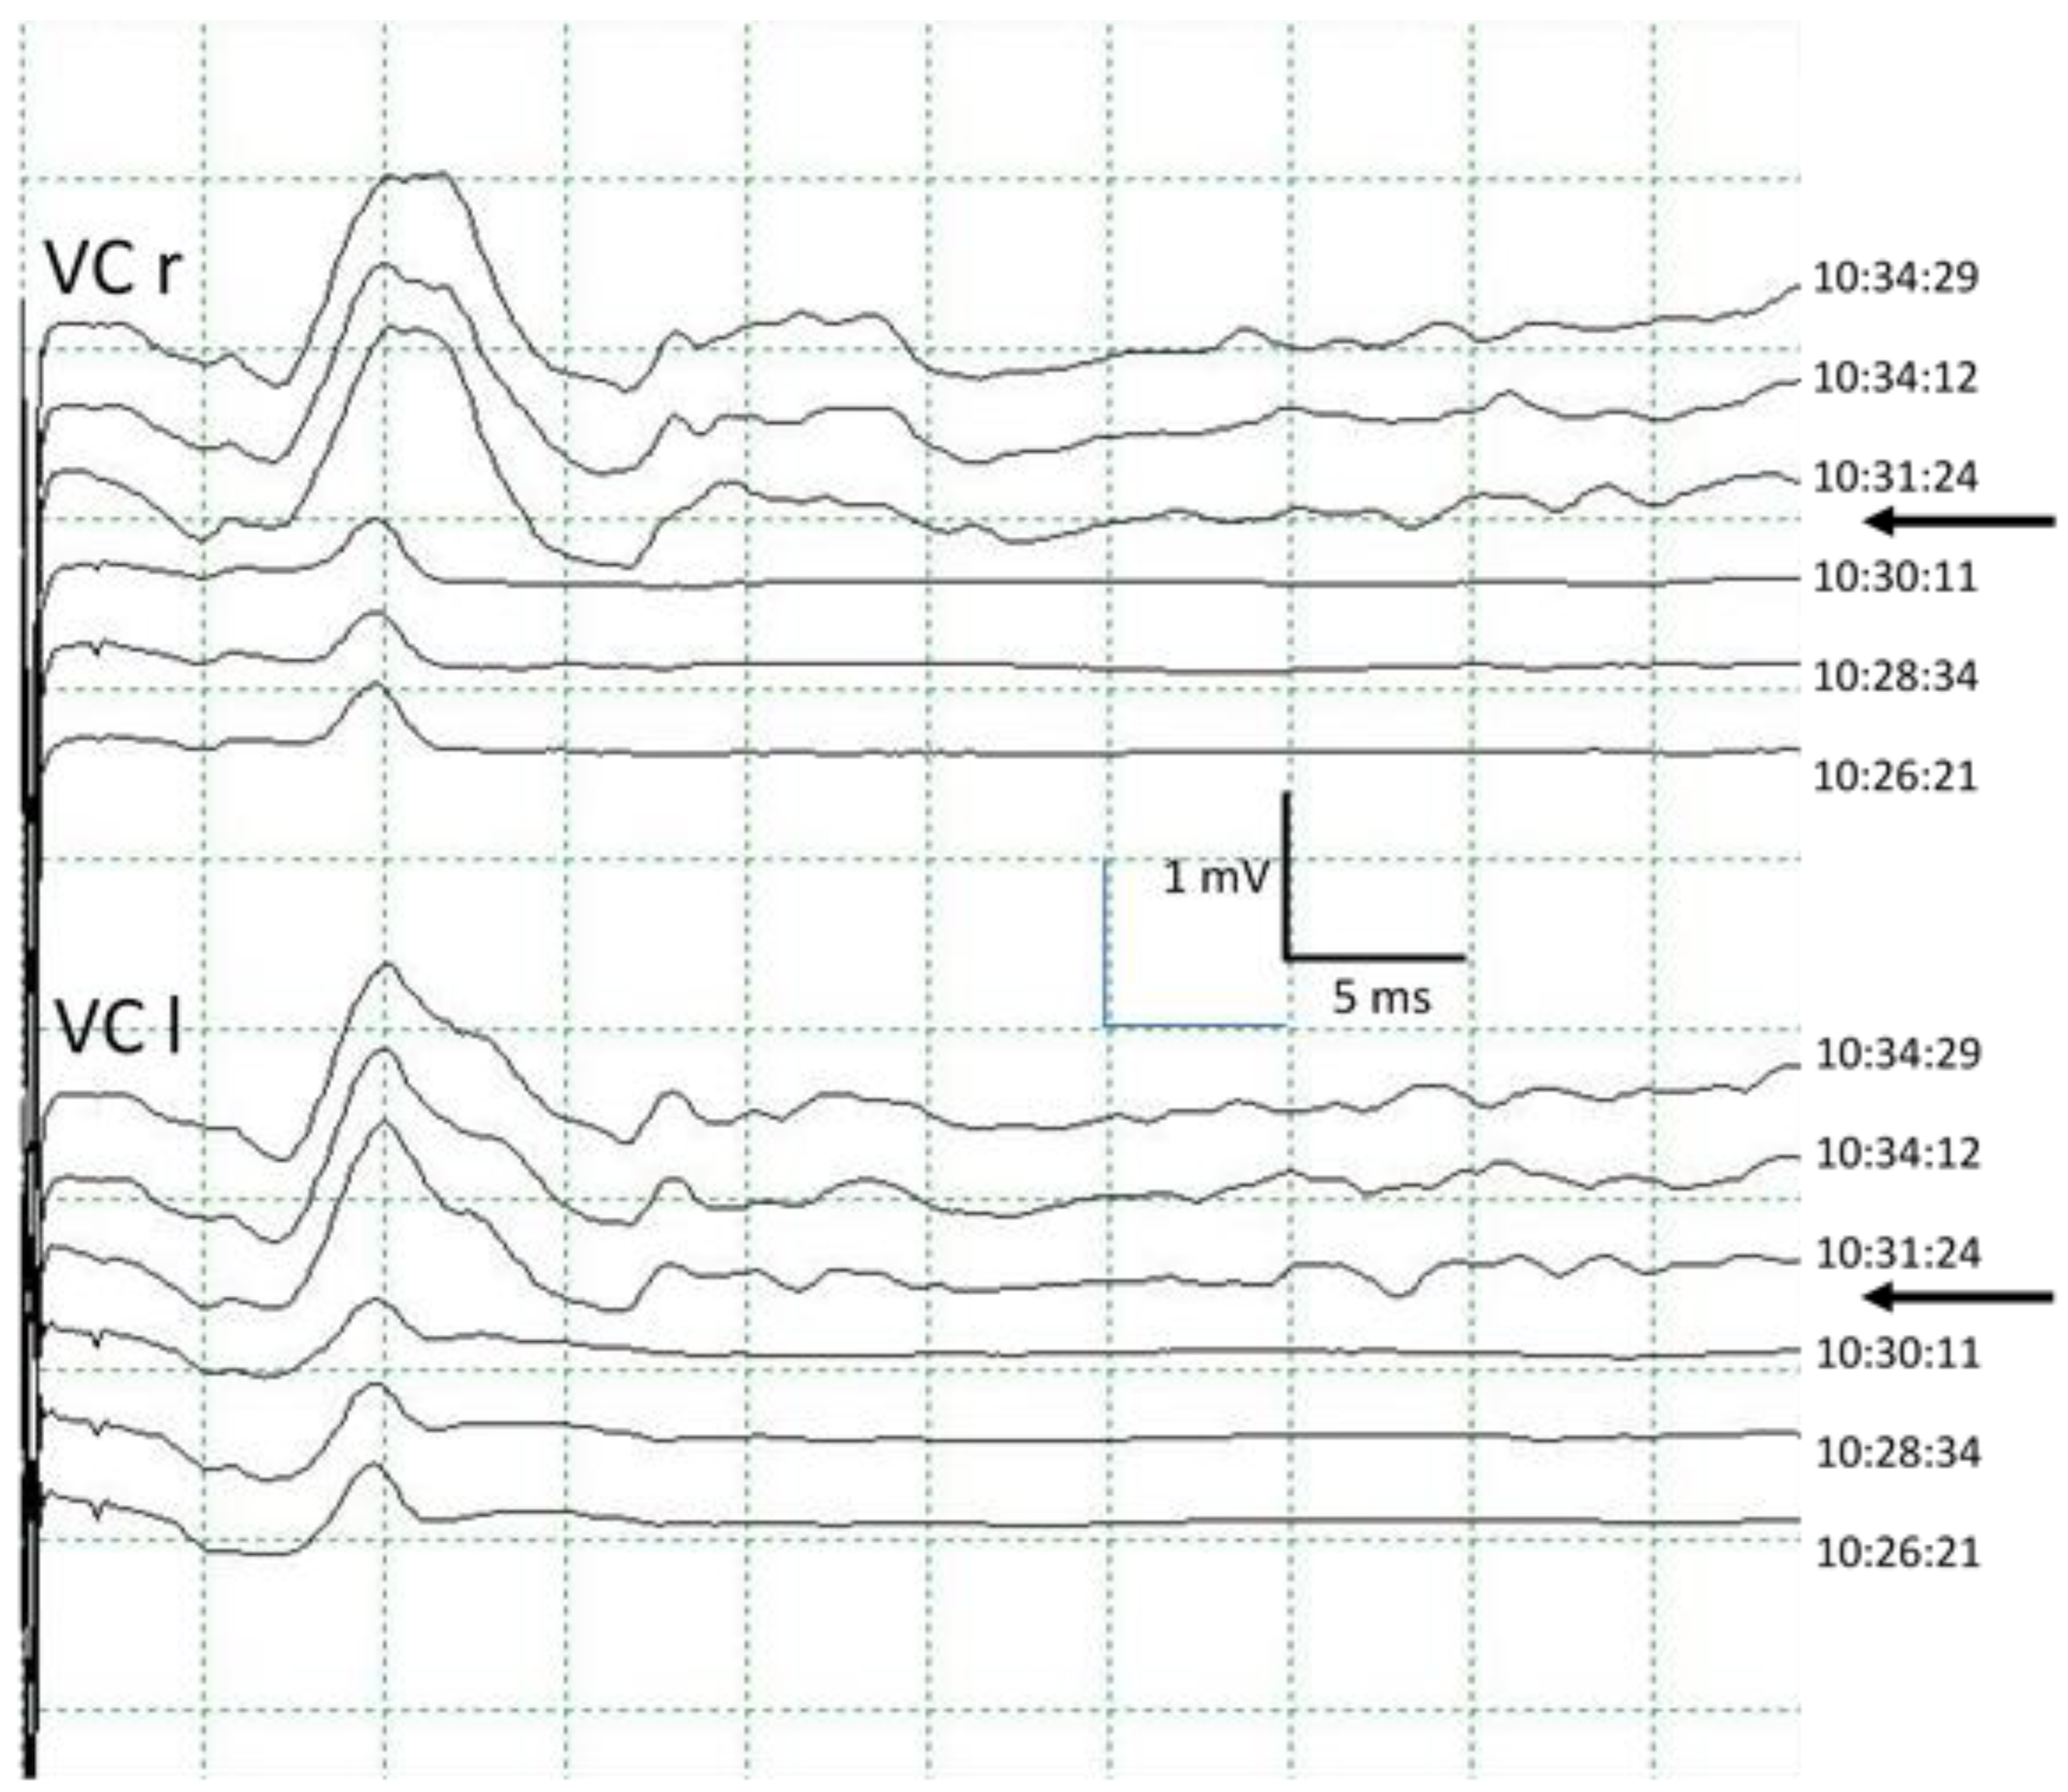

The morphology of the CMAP obtained in VC after ESVNCT has the same behavior with both stimulation techniques. It is variable, bi, or polyphasic. This variability is probably due to the characteristics of the recording electrode placed in the orotracheal tube. It presents several recording points located longitudinally allowing, theoretically, for the differentiation between the right and left side. In practice, however, this is not always the case, obtaining instead bilateral CMAP with unilateral stimulation (Figure 3). During the dissection of the thyroid gland, displacement of the larynx occurs very frequently, which we recorded in the cEMG as a movement artifact. This can also result in small movements of the tube from rotation or sliding and changes in the spatial relationship of the electrode recording areas with the VC, which results in changes in the CMAP both in morphology and amplitude. This should not be confused with signs of RLN injury [6] (Figure 6).

Figure 6.

Immediate change in the morphology of the CMAP in the vocal cords when the orotracheal tube is repositioned (arrows), producing a significant increase in its amplitude. VC: vocal cord. r: right. l: left.